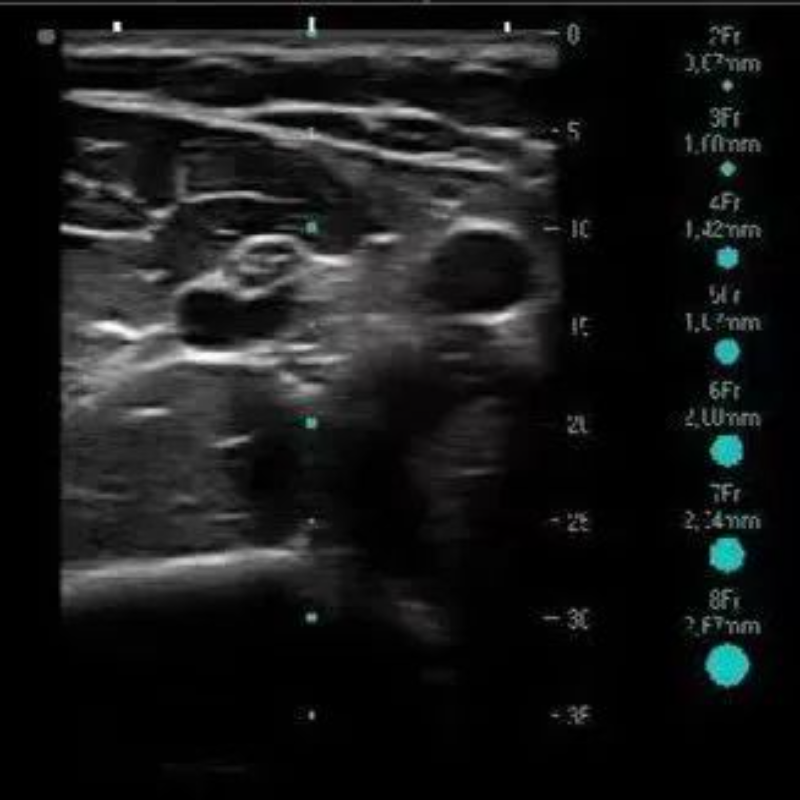

近日,我院腫瘤科成功開展了B超下中等長度導管置入新技術,該項技術對提升我院靜脈輸液護理質(zhì)量,推進新技術、新理念、新規(guī)范有著重要意義。患者患者反復住院治療或輸液療程長導致外周血管條件差,靜脈穿刺困難。為解決這一難題,腫瘤科護理團隊開展了B超下中等長度導管置入新技術。

導管置入術由靜脈治療專科護士王敏娜實施,采用超聲引導技術,將導管經(jīng)患者上臂貴要靜脈置入,導管尖端位置到達鎖骨下靜脈。置入中長導管后患者無需重復穿刺,輸注刺激性藥物無疼痛,受到患者及家屬的好評。

此項技術的成功開展,標志著我院靜脈輸液水平成功邁上新臺階。從“無針化治療”到“一針化管理”,樹立了安全的靜脈治療理念。在提高工作效率的基礎上,進一步提升我院的靜脈治療質(zhì)量,減輕患者痛苦及外周血管的損傷,保護患者血管通路,從而給患者帶來更加安全、專業(yè)、舒適的就醫(yī)體驗。